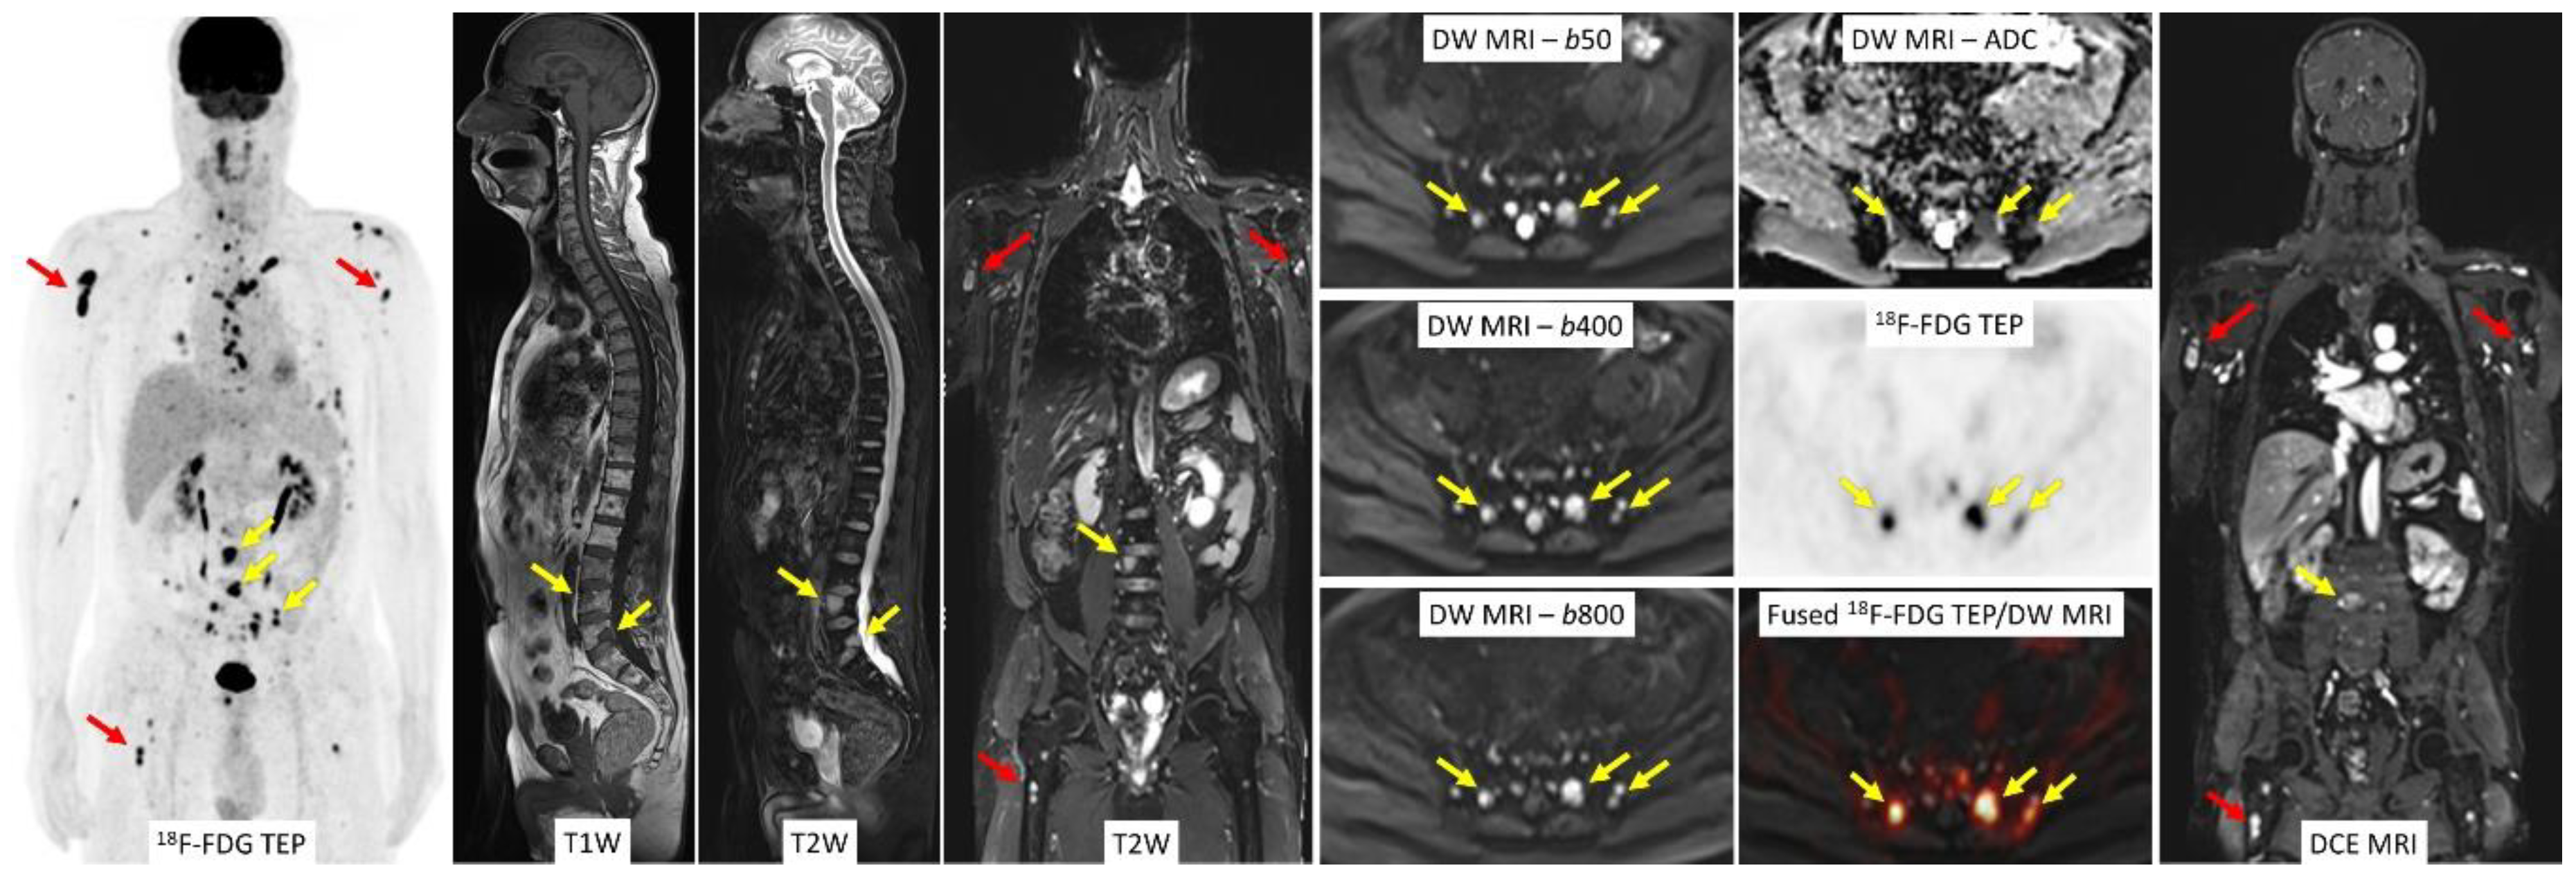

2.3. Whole-Body Diffusion-Weighted Imaging

2.4. Whole-Body Dynamic Contrast-Enhanced MRI

3. 18F-FDG PET/MRI